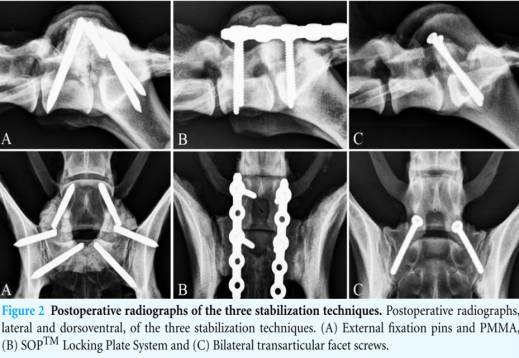

- Methoden

- Verplattung

- transartikuläre Schrauben durch Fasettengelenke

- Gewindepins + Knochenzement